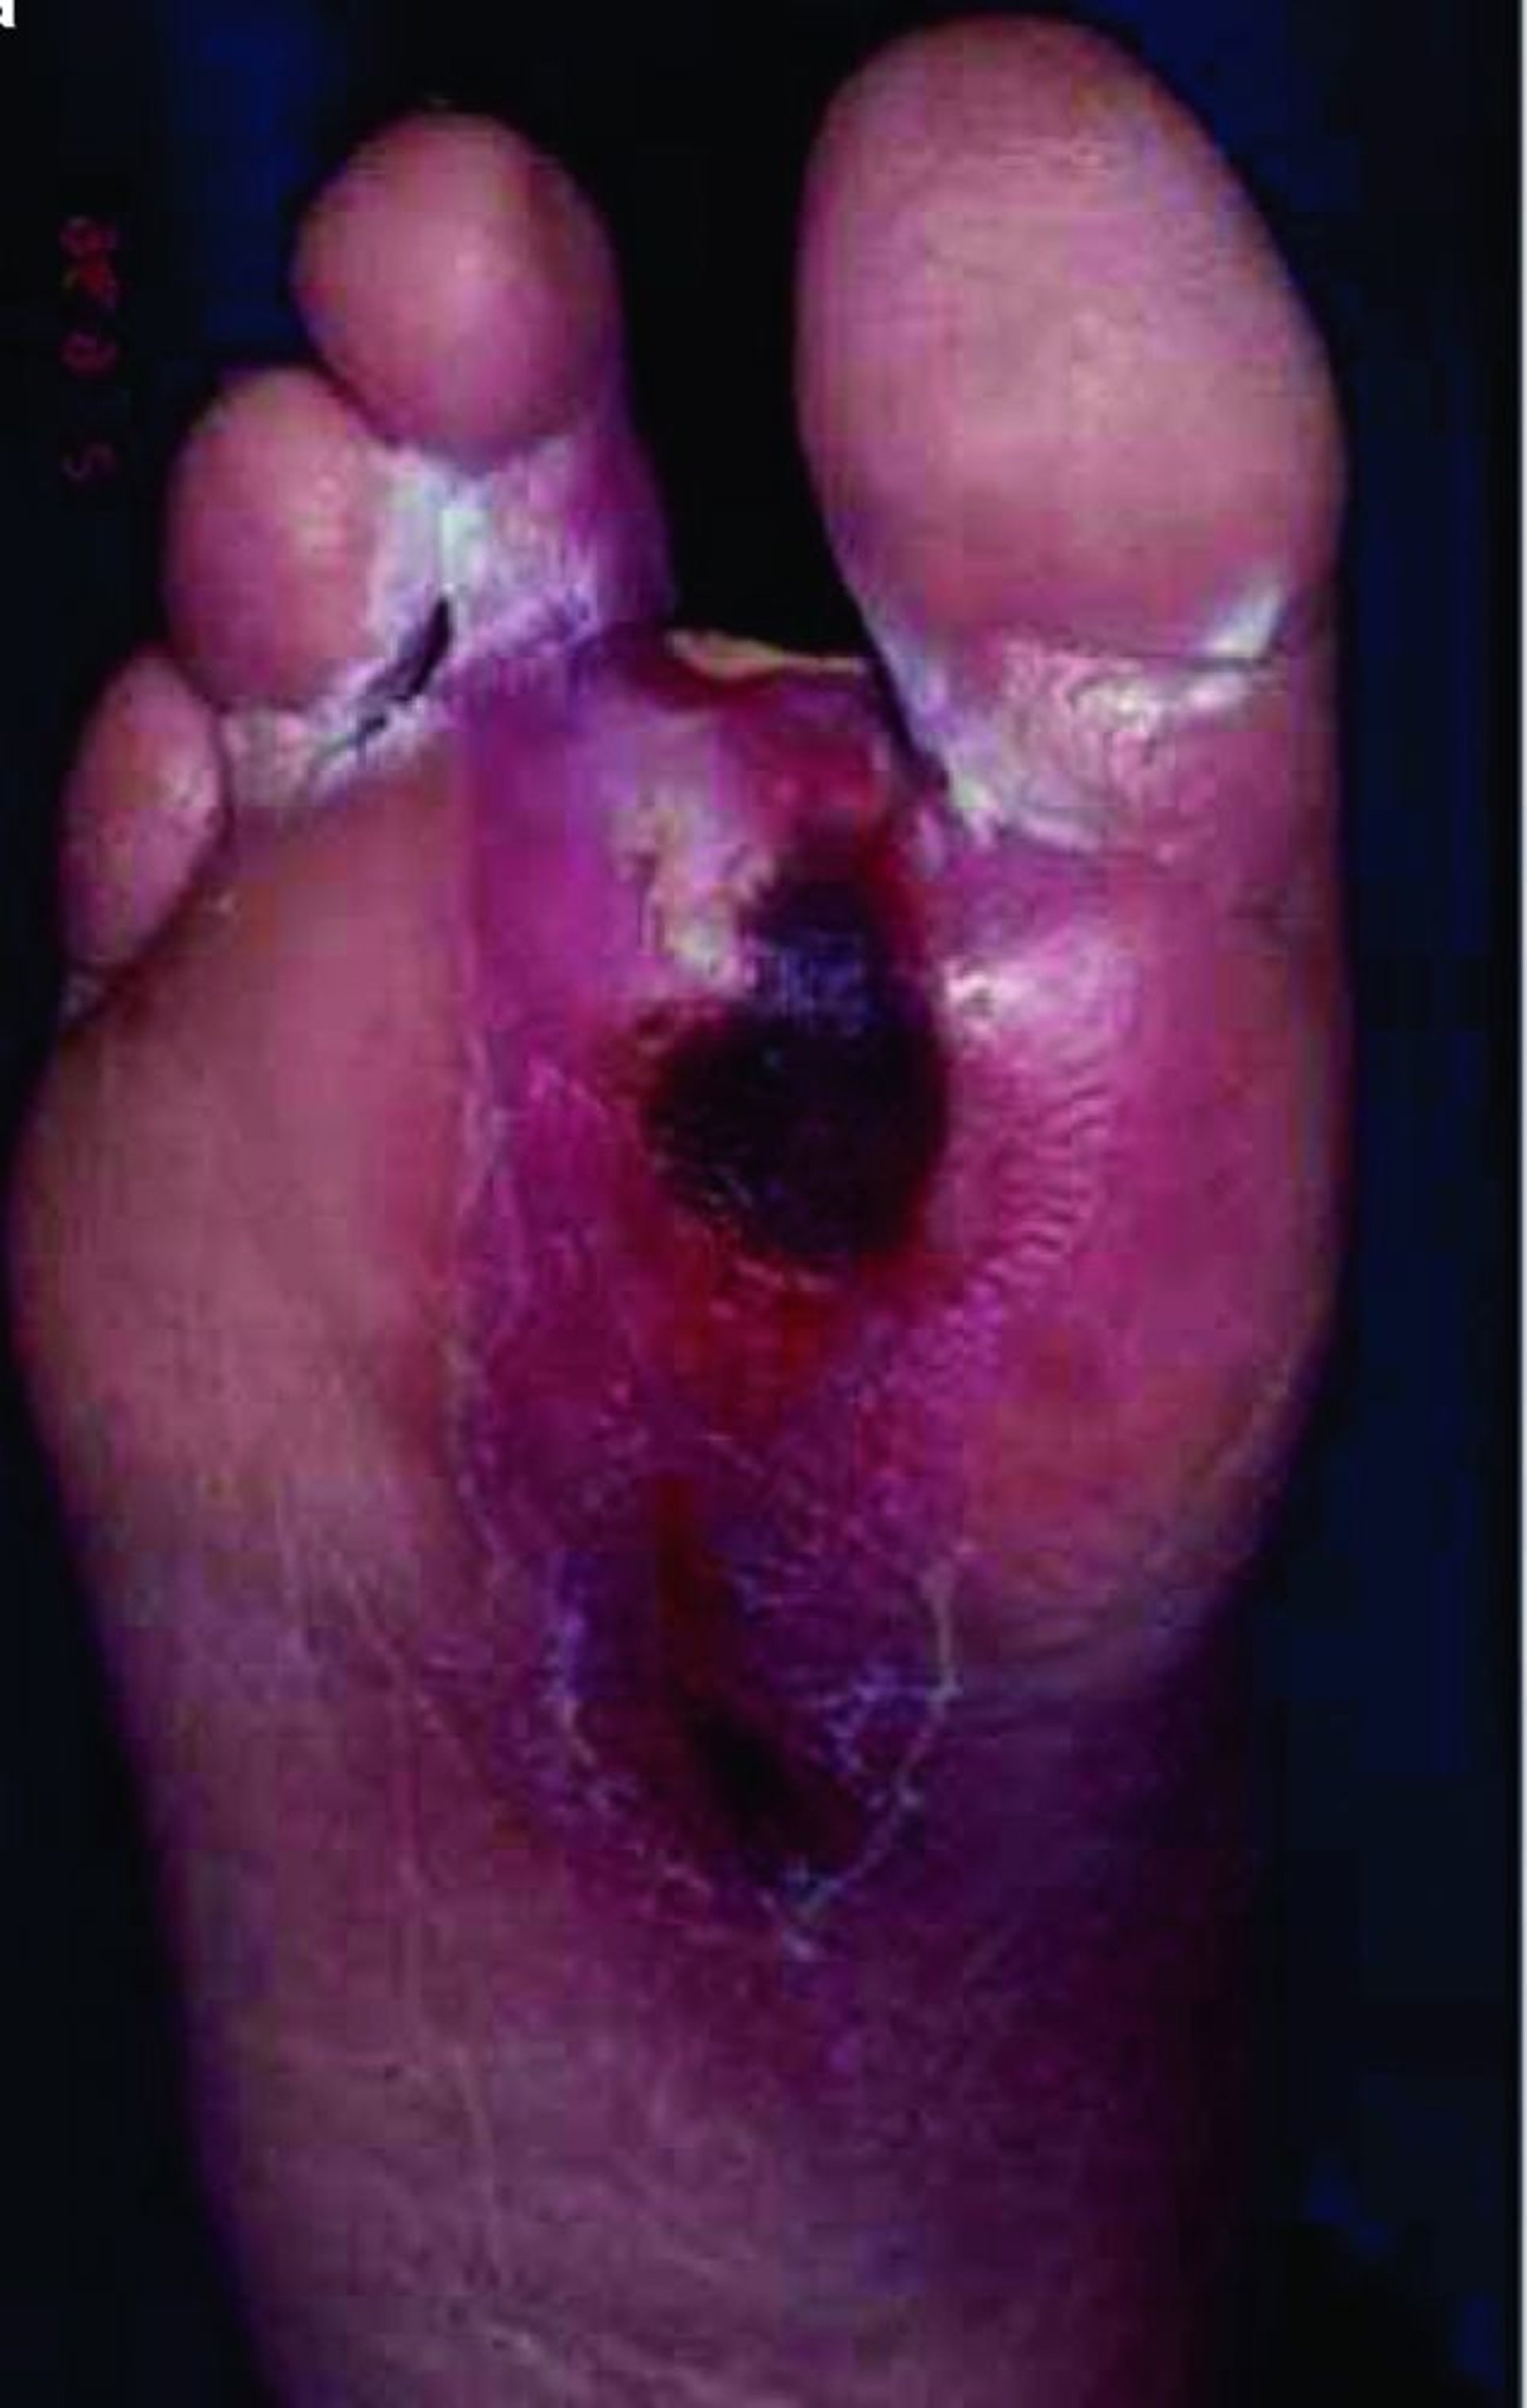

Úlcera del pie

En esta foto se observa una úlcera de gran tamaño en la planta del pie. Las personas con diabetes son particularmente propensas a tener úlceras en los pies y las piernas.